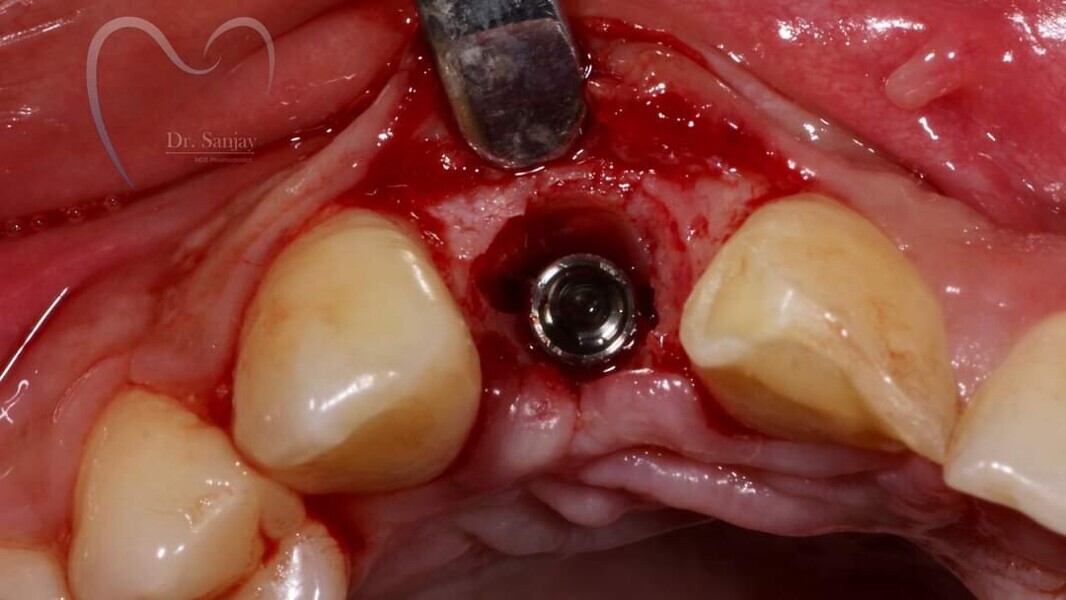

Esthetic Rehabilitation of Maxillary Anterior Teeth: Dr Sanjay Sah